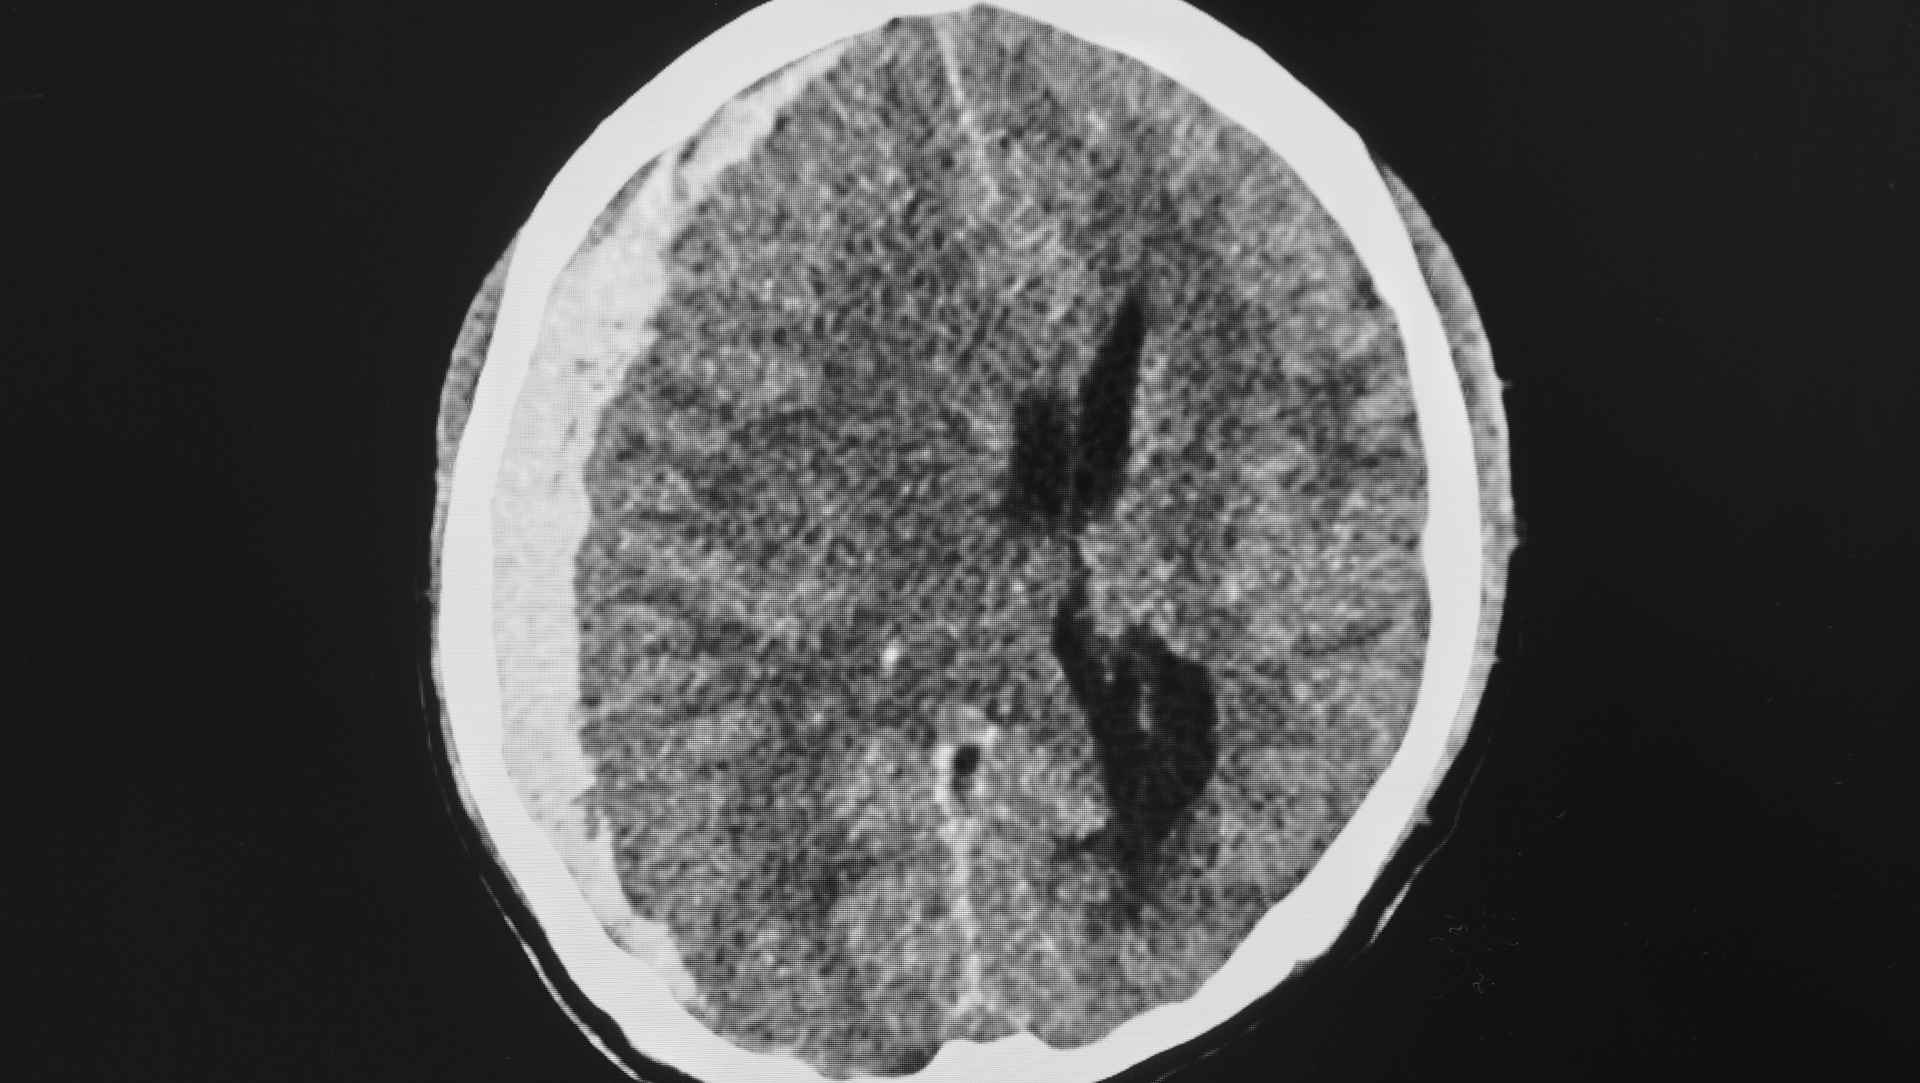

• Globally, access to ICP monitors is variable; the trialists sought evidence relevant to both high-resource and resource-limited environments where clinicians rely on neurological examination and CT imaging.

• Imaging–clinical examination strategy (Imaging–Clinical Examination Group): tiered management driven by scheduled/triggered CT imaging and neurological examination (including deterioration signals and radiological signs of raised ICP), without continuous ICP data.

• Co-interventions: the same broad categories of brain-directed therapies were available, but their initiation/escalation was triggered by clinical/CT criteria rather than ICP/CPP thresholds.